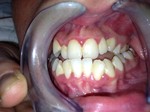

Scopri come era questa bocca prima del trattamento presso la clinica dentistica del Dott. Gabriele Mirabella

clicca se vuoi vedere il quadro clinico iniziale e vedrai che anche tu puoi avere il sorriso che hai sempre desiderato